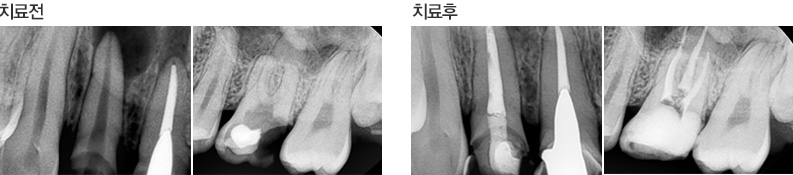

아프지 않다고 잘 된 신경 치료가 아닙니다.

감염된 신경을 완벽히 제거해야 치아를 건강하게 오래 사용할 수 있습니다.